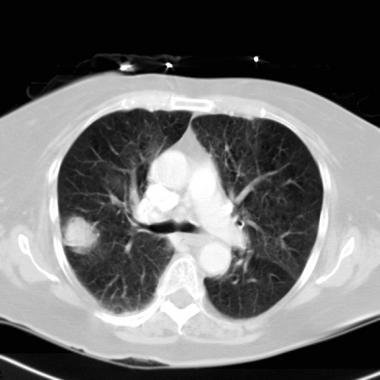

Computed Tomography Scan

(CT Scan)

- More powerful ionizing radiation than X-ray

Takes a 360-degree image of internal organs, spine, and vertebrae

- Gives pictures in cross-sections

- More detailed look at organs, soft tissue, blood vessels

- Better diagnostic for cancer, heart disease, infection

- More expensive than X-ray